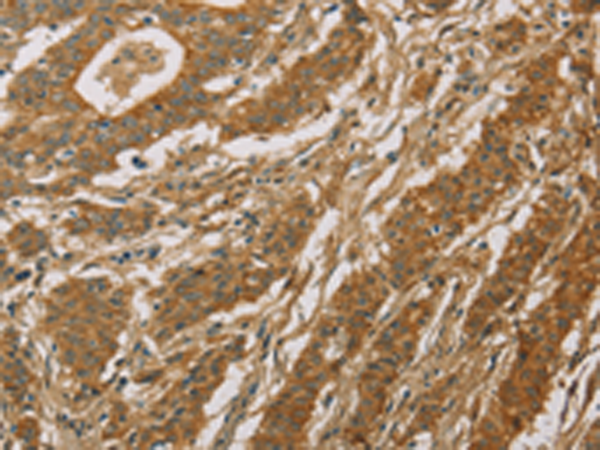

分类: 科研抗体货号: P08197别名: FHI; CPN1; CYP11B; P450C11应用: IHC反应种属: Human